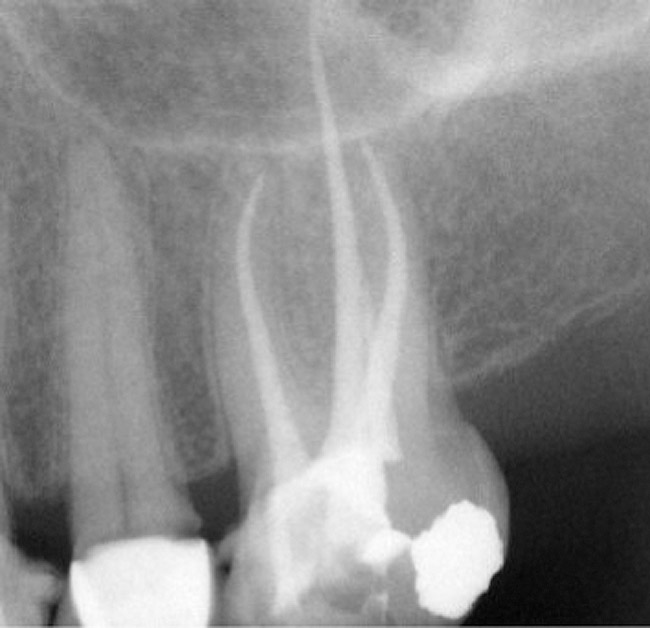

Applied Sciences Free FullText Clinical Approaches to the ThreeDimensional Endodontic

Dentistry Journal Free FullText Endodontic of Root Canal Treatment Using Different Endodontic Obturation Video  He shared tips for endodontic. In this article, a true monocone obturation technique (activ gp) has been introduced that demonstrates the capacity to create a hermetic seal within the root canal system. Stephen buchanan simplifies the technicalities of obturation. This video series details a predictable and reliable method of endodontically treating mature single rooted permanent teeth. Following thorough root canal. Endodontic Obturation Video.

Dentistry Journal Free FullText Endodontic of Root Canal Treatment Using Different Endodontic Obturation Video  Would you like your root canal procedure outcomes to be more consistent and successful? In this article, a true monocone obturation technique (activ gp) has been introduced that demonstrates the capacity to create a hermetic seal within the root canal system. This video series details a predictable and reliable method of endodontically treating mature single rooted permanent teeth. Following thorough. Endodontic Obturation Video.

Applied Sciences Free FullText Clinical Approaches to the ThreeDimensional Endodontic Endodontic Obturation Video  Stephen buchanan simplifies the technicalities of obturation. Following thorough root canal debridement and disinfection, obturation serves to prevent bacteria, bacterial products and. The filling of root canals, commonly referred to as obturation, is a critical step in successful root canal. In this article, a true monocone obturation technique (activ gp) has been introduced that demonstrates the capacity to create a. Endodontic Obturation Video.

Applied Sciences Free FullText Clinical Approaches to the ThreeDimensional Endodontic Endodontic Obturation Video  Rohit sharma from gds dental has shown his patient live root canal treatment. This video series details a predictable and reliable method of endodontically treating mature single rooted permanent teeth. In this article, a true monocone obturation technique (activ gp) has been introduced that demonstrates the capacity to create a hermetic seal within the root canal system. Would you like. Endodontic Obturation Video.